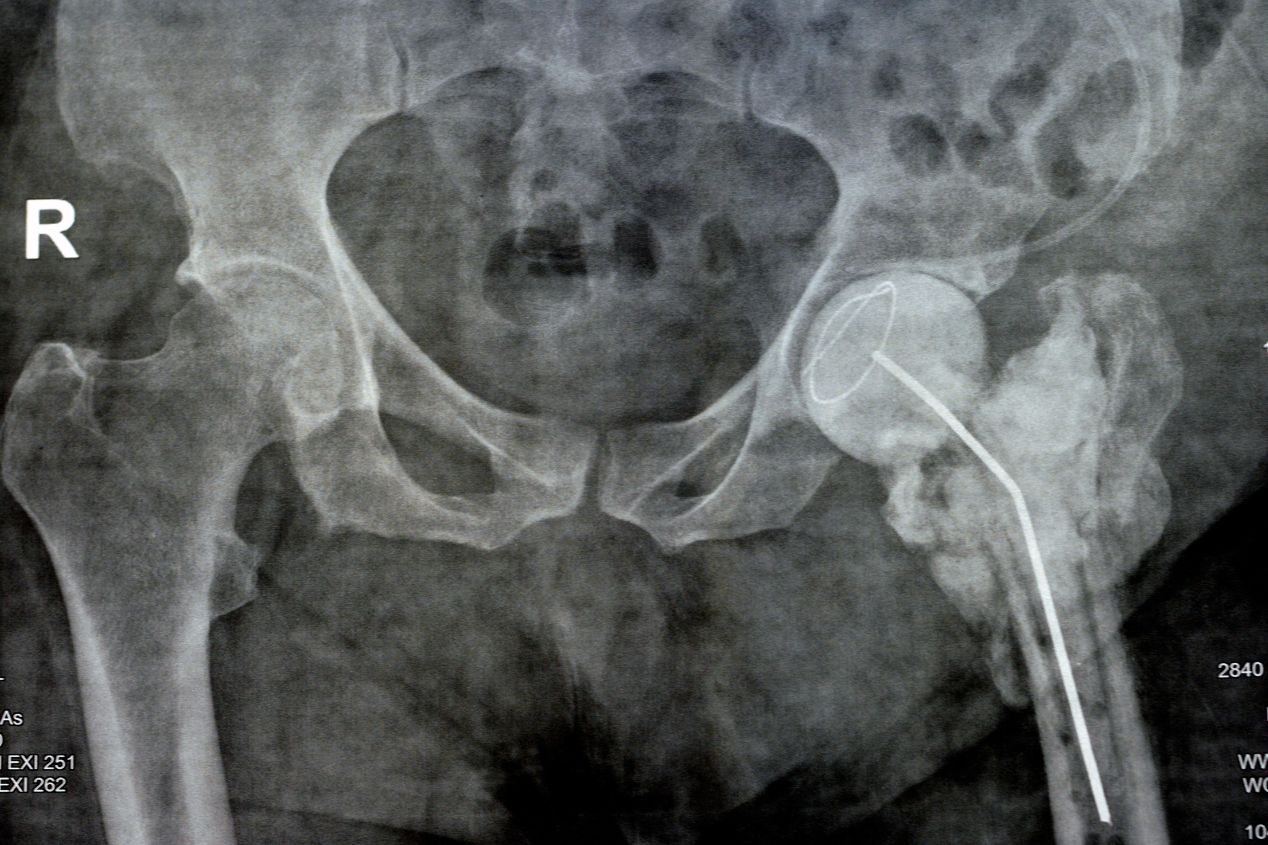

Η σημασία της γρήγορης χειρουργικής αντιμετώπισης καταγμάτων ισχίου

Η γρήγορη χειρουργική αντιμετώπιση καταγμάτων ισχίου αποτελεί κρίσιμη παρέμβαση που μπορεί να σώσει ζωές και να βελτιώσει σημαντικά την ποιότητα ζωής των ασθενών. Τα κατάγματα ισχίου αποτελούν μια σοβαρή κατάσταση που αφορά κυρίως τους ηλικιωμένους ανθρώπους, αλλά μπορεί να επηρεάσει και άλλες ηλικιακές ομάδες. Η σωστή και γρήγορη αντιμετώπιση αυτών των καταγμάτων είναι απαραίτητη για πολλούς λόγους.   Μείωση του κινδύνου επιπλοκών: Τα κατάγματα ισχίου μπορεί να οδηγήσουν σε σοβαρές επιπλοκές, όπως λοίμωξη, θρόμβωση, πνευμονία και εμβολή. Η γρήγορη χειρουργική αντιμετώπιση μειώνει αυτούς τους κινδύνους και βελτιώνει τις προοπτικές ανάρρωσης Γρήγορη επάνοδο στην όρθια θέση και βάδιση.  Οι ασθενείς που υποβάλλονται σε γρήγορη χειρουργική αντιμετώπιση καταγμάτων ισχίου μπορούν να ανακτήσουν την ανεξαρτησία τους πολύ γρηγορότερα. Αυτό συμβάλλει στην αποφυγή μακροχρόνιων αναπηριών και επαναφέρει την κινητικότητα και την ποιότητα ζωής τους. Οικονομικά οφέλη: Η γρήγορη αντιμετώπιση καταγμάτων ισχίου μειώνει τον χρόνο νοσηλείας και την ανάγκη για μακροχρόνια φροντίδα. Αυτό μειώνει το οικονομικό βάρος τόσο για τον ασθενή  για τον υγειονομικό φορέα και ολόκληρη την κοινωνία. Προσωπική ανεξαρτησία: Η γρήγορη αντιμετώπιση επιτρέπει στους ασθενείς να διατηρήσουν την ανεξαρτησία τους, να συνεχίσουν τις καθημερινές δραστηριότητές τους και να ζήσουν μια πιο πλήρη ζωή. Ψυχολογική ευεξία: Η γρήγορη αντιμετώπιση βοηθά στη μείωση του ψυχολογικού τραύματος που προκαλείται από τον τραυματισμό. Οι ασθενείς που αναρρώνουν ταχύτερα έχουν συνήθως λιγότερο άγχος και καλύτερη ψυχολογική ευεξία.   Συνολικά, η γρήγορη χειρουργική αντιμετώπιση καταγμάτων ισχίου είναι ζωτικής σημασίας για την ασφάλεια, την ανεξαρτησία και την ποιότητα ζωής των ασθενών. Οι ασθενείς, οι οικογένειές τους και οι υγειονομικοί φορείς πρέπει να ενισχύουν την ευαισθητοποίηση και την πρόσβαση σε γρήγορες και αποτελεσματικές υπηρεσίες αντιμετώπισης τέτοιων καταγμάτων, προκειμένου να εξασφαλίσουν την καλύτερη δυνατή φροντίδα για τους ασθενείς.